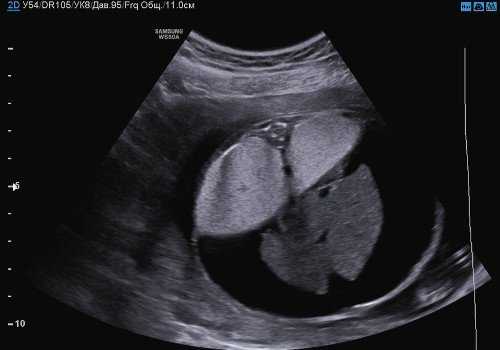

При оценке грудной клетки на уровне четырехкамерного среза сердца были выявлены увеличенные в размерах, гиперэхогенные легкие и сдавленное сердце, которое занимало меньше 1/6 поперечного сечения грудной клетки. В области трахеи определялось анэхогенное аваскулярное округлое образование (рис. 1).

Рис. 1. Поперечный срез грудной клетки на уровне четырехкамерного среза сердца. Увеличенные гиперэхогенные легкие плода, сдавленное, уменьшенное в размерах сердце и трахея, определяющаяся как округлое анэхогенное образование кпереди от позвоночника.